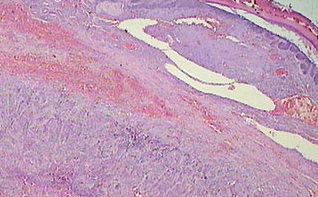

hidradenoma-malignant nodular hidradenoma = الغدوم العرقي الخبيث _الغدوم العرقي العقيدي